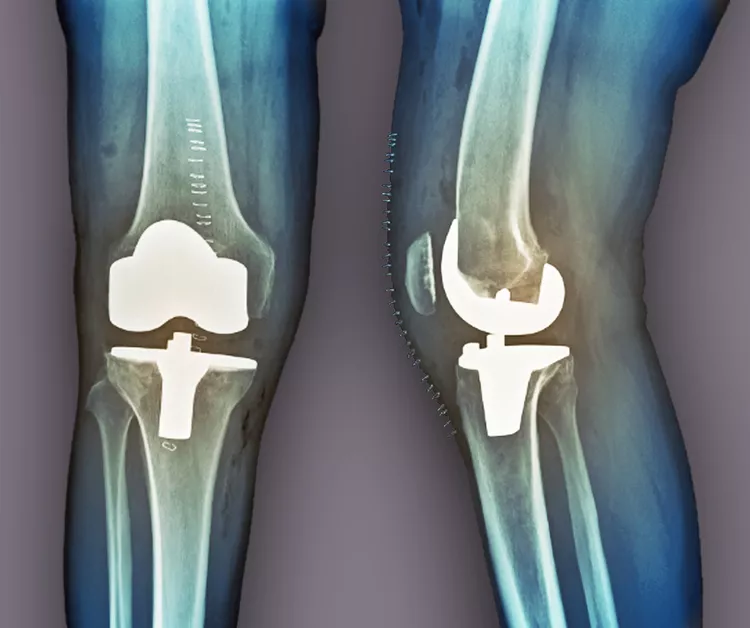

當(dāng)其他療法失敗時(shí),關(guān)節(jié)置換術(shù)是最后選擇。在這種手術(shù)中,醫(yī)生會(huì)切除膝蓋受損部位,并用金屬或塑料部件代替。如果這種方法不起作用,通過(guò)融合連接骨頭可能會(huì)緩解疼痛。缺點(diǎn)是,在這種手術(shù)后,其他關(guān)節(jié)最終會(huì)承受更大的壓力,以補(bǔ)償融合關(guān)節(jié)的運(yùn)動(dòng)損失。